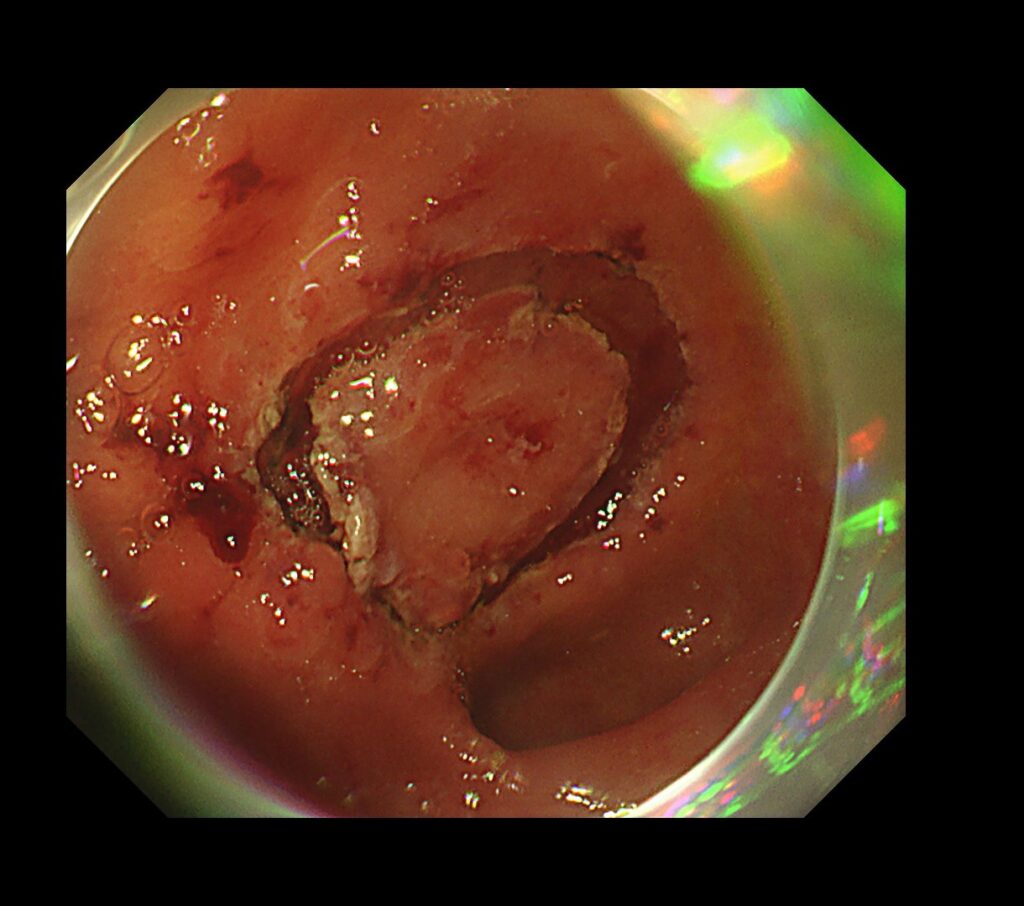

水浸下に、電気メスでマーキングを丁寧に行います。

硬そうな瘢痕近傍に癌があることが、みてとれると思います。

局所注射を粘膜下に施行し、電気メスで全集切開を行います。